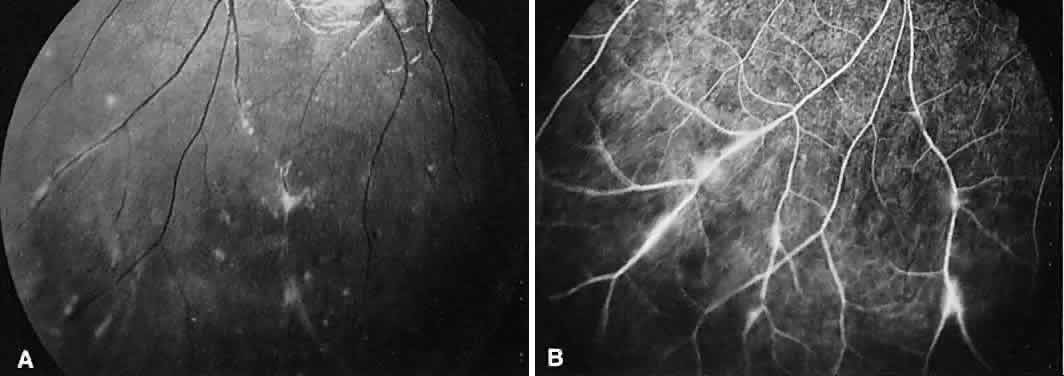

INTERMEDIATE UVEITIS

Intermediate uveitis is also known as pars planitis, peripheral uveitis, and chronic cyclitis. Intermediate uveitis is an inflammatory disease that affects young adults, causing symptoms of photophobia, floaters, and blurry vision. Clinically, mild anterior chamber inflammation, vitreous cells, vitreous snowballs, inflammatory membranes on the pars plana, phlebitis, cystoid macular edema, and, rarely, choroidal and retinal neovascularization are seen.

On fluorescein angiography, there is venular wall staining (Fig. 9),30 hyperfluorescence, and leakage of the peripheral inflammatory membranes.31 Cystoid macular edema often is evident.30 Optic disc, peripheral retinal, and subretinal32–34 neovascularization are rare.

Fig. 9. Intermediate uveitis. A. Red-free photography of the peripheral retina shows sheathing of the retinal venules. B. Fluorescein angiography shows staining of the vessel walls with leakage from the peripheral venules.

BIRDSHOT RETINOCHOROIDOPATHY

Birdshot retinochoroidopathy (also known as vitiliginous chorioretinitis) presents bilaterally, generally in middle-aged women, causing floaters and decreased vision, night blindness, and color blindness. Clinically, there are patches of postequatorial choroidal and retinal pigment epithelial depigmentation (Fig. 10A), vitreous cells, macular and disc edema, and venous sheathing. SRNV frequently is a late sequela. Often central vision may be preserved in at least one eye.

Fig. 10. Birdshot retinochoroidopathy. A. Multiple cream-color deep choroidal lesions. B. Fluorescein angiogram shows leakage of the optic disc and the retinal vasculature. C. Indocyanine green angiography showing areas of hypofluorescence that exceed those observed on fluorescein angiography.

On fluorescein angiography, retinal vessel staining, disc leakage, and cystoid macular edema are found (see Fig. 10B). There often is generalized hypofluorescence of the retinal vessels and increased circulation time.35,36 Surprisingly, the patches of depigmentation may appear normal on angiography, although there can be mild late hyperfluorescence.35,36 Posterior pole choroidal hyperfluorescent lesions that correspond to the areas of depigmentation and SRNV also can be seen.37

On ICG angiography (see Fig. 10C), early and late hypofluorescent patches, exceeding the clinically detectable lesions, with a choroidal vasotropic distribution and relative sparing of the peripapillary area and the central macula, are noted. These findings differentiate this condition from AMPPPE, multifocal choroiditis, and other granulomatous conditions such as sarcoidosis and sympathetic ophthalmia. Rarely, hyperfluorescent spots are noted in the late phases of the angiogram, which correspond ophthalmoscopically to retinal inflammation or obstructive changes.38